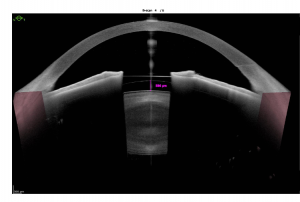

There are several methods used to obtain the variables that are required to calculate pIOL power. Refraction can be performed by manifest refraction or autorefraction. ACD and angle-to-angle distance are best-obtained using optical coherence tomography (OCT), but can also be measured using ultrasound biomicroscopy (UBM) or Scheimpflug imaging. ACD is measured from the corneal apex to the anterior surface of the crystalline lens, and is use to calculate effective lens position (ELP) in PCIOLs by substracting the distance between the pIOL and the crystalline lens from the ACD. The ELP is typically 0.8mm in the Artisan/Verisyse lens.[9] White-to-white (WTW) measurement with an IOL-Master or calipers can be used to estimate angle-to-angle distance. Corneal power is calculated using keratometry or topography to measure the curvature of the cornea.[6][9] Different nomograms optimized PCIOL (Visian ICL) sizing based on swept-source anterior segment optical coherence tomography.[10] Ideally the distance between the PCIOL and the crystalline lens (vault) should vary between 200 and 800 microns and can be measured by anterior segment OCT (figure 9).